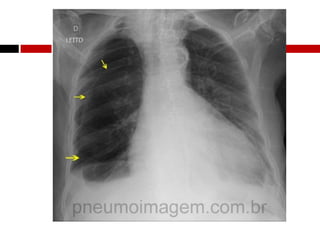

Interpretação radiológica

Fisiopatologia

 Redução dos volumes pulmonares

 Diminuição da Complacência Pulmonar

 Reduz a capacidade de difusão

 Hipoxemia se 50% do pulmão for afetado

 Efeito “shunt”

 Dependente da condição respiratória subjacente